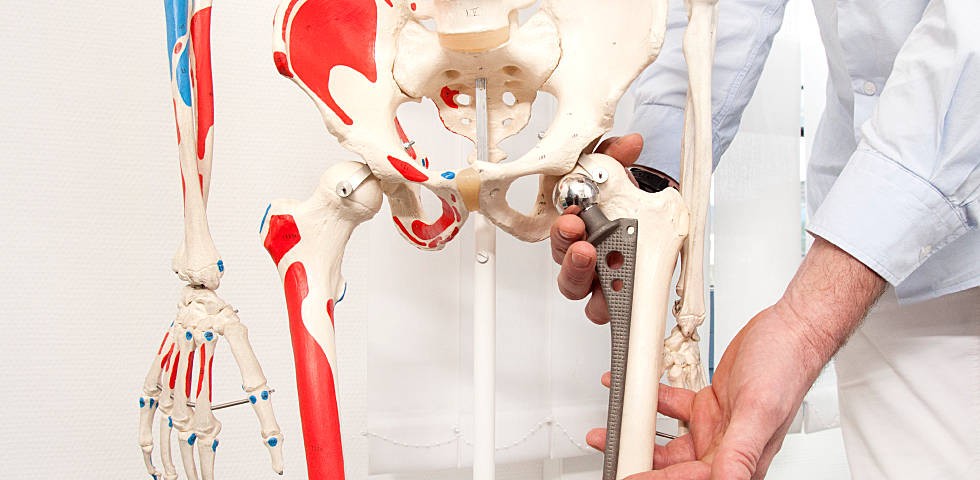

Эндопротезирование тазобедренного сустава: фото и схемы